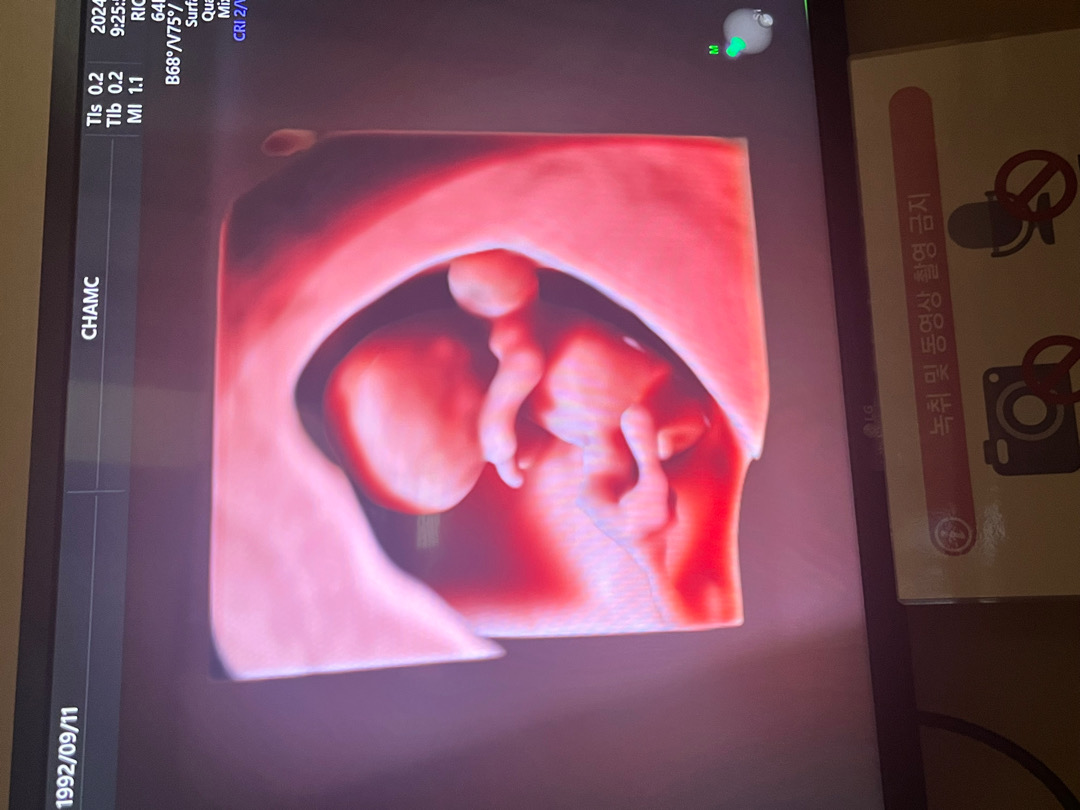

기적과도 같은 확률로 아기 천사 만나서 10주에요 오늘 난임병원도 졸업했답니다 ❤️ 오늘 입체초음파 봤어요 너무너무 귀엽죠?!

어머나 저도 오늘10주됬는데 아가가 팔다리가 기네요 저는 초음파만봐서 잘모르겟는데.넘귀엽네요^^❤️